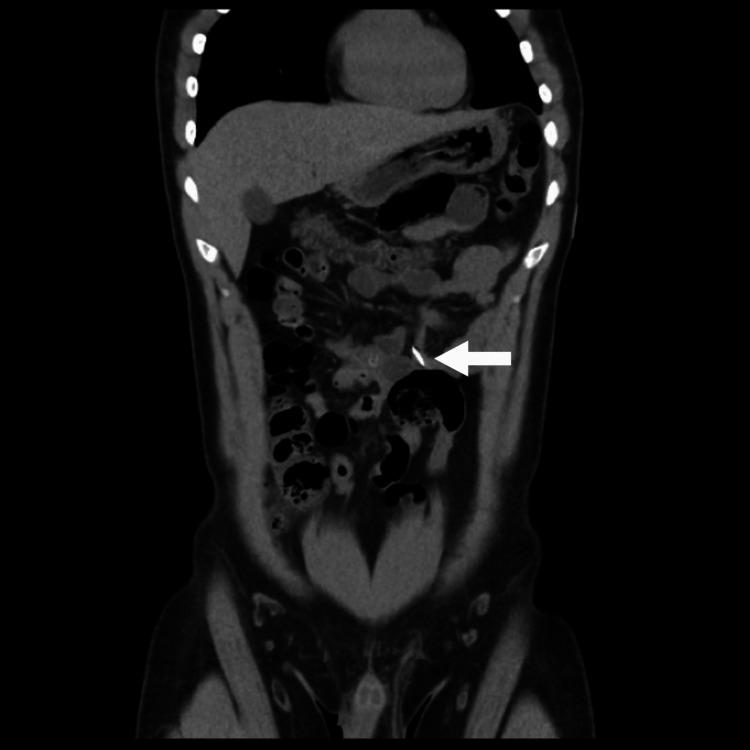

Intentional foreign body ingestion is the phenomenon wherein one swallows a non-digestible object with the intent to cause self-injury. It is intentional in adult patients with a positive psychiatric history and can be a recurrent issue. Although the incidence of this condition is increasing, there are few existing articles on the subject that highlight its importance. This case report aims to present a unique patient encounter to emphasize the multispecialty approach required for management and provide an overview of the literature available on the subject regarding types of objects swallowed, selection of appropriate imaging modalities, and plans of management.